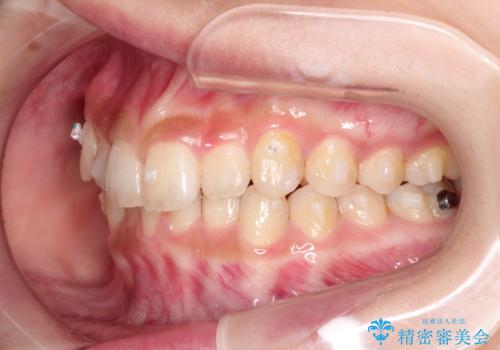

- 前歯のガタガタを主訴に来院された患者様です。

八重歯になっており、下顎の前歯が上顎の前歯に隠れてしまう、ディープバイトという状態でした。

インビザラインを使用して矯正する計画としました。

ディープバイトの場合、ワイヤー装置の装着が難しいことがあります。

インビザラインではかみ合わせに左右されず装着できるメリットがあり、ワイヤーに比べインビザラインの方が治療しやすい場合もあります。